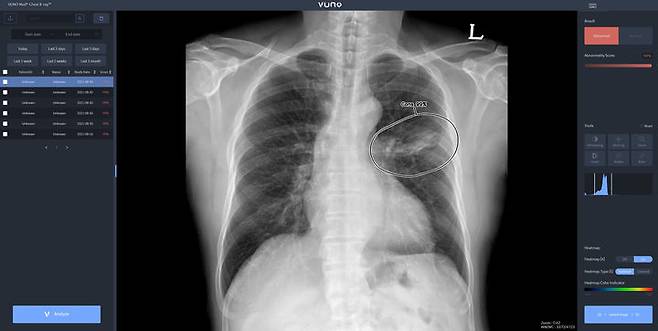

![[서울=뉴시스] 26일 의료 인공지능(AI) 뷰노에 따르면 뷰노 메드 체스트 엑스레이는 흉부 엑스레이 영상을 분석해 주요 5개 소견(결절·경화·간질성 음영·흉막 삼출·기흉) 유무를 검출하고 소견의 조합을 통해 판독 가능한 관련 질환(결핵·폐렴)을 제시한다. 높은 판독 정확성으로 임상 환경에서 의료진의 영상 판독 및 폐질환 진단을 보조한다. (사진=뷰노 제공) 2025.03.28. photo@newsis.com *재판매 및 DB 금지](https://img1.daumcdn.net/thumb/R658x0.q70/?fname=https://t1.daumcdn.net/news/202509/26/newsis/20250926093649409dvry.jpg)